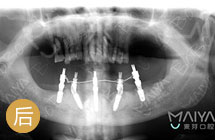

5颗钉恢复半口牙,七旬老汉乐开花!

手术成功原理:传统种牙一个萝卜一个坑太难受,为让七旬老李少遭罪,麦芽医生团前期通过牙周洁治,为其量身定制了“ALL-ON-5”种植方案,增加负重与咀嚼能力,总共恢复12颗牙齿… [详细]

节省近1/3费用

当天戴冠能饮食

远期结合更稳固

创口减少近2/3